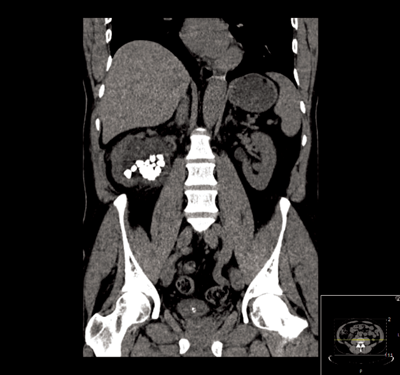

A 76-year-old male with end stage renal failure due to obstructive uropathy from benign prostatic enlargement was transferred from a referring hospital. A right ureteric stent had been placed and a left sided stent was sited too far proximally in the ureter (Figure 1). Comorbidity included ischaemic heart disease, cardiac failure and the patient was anti-coagulated. There had been one failed attempt to re-position the stent.

Figure 1.